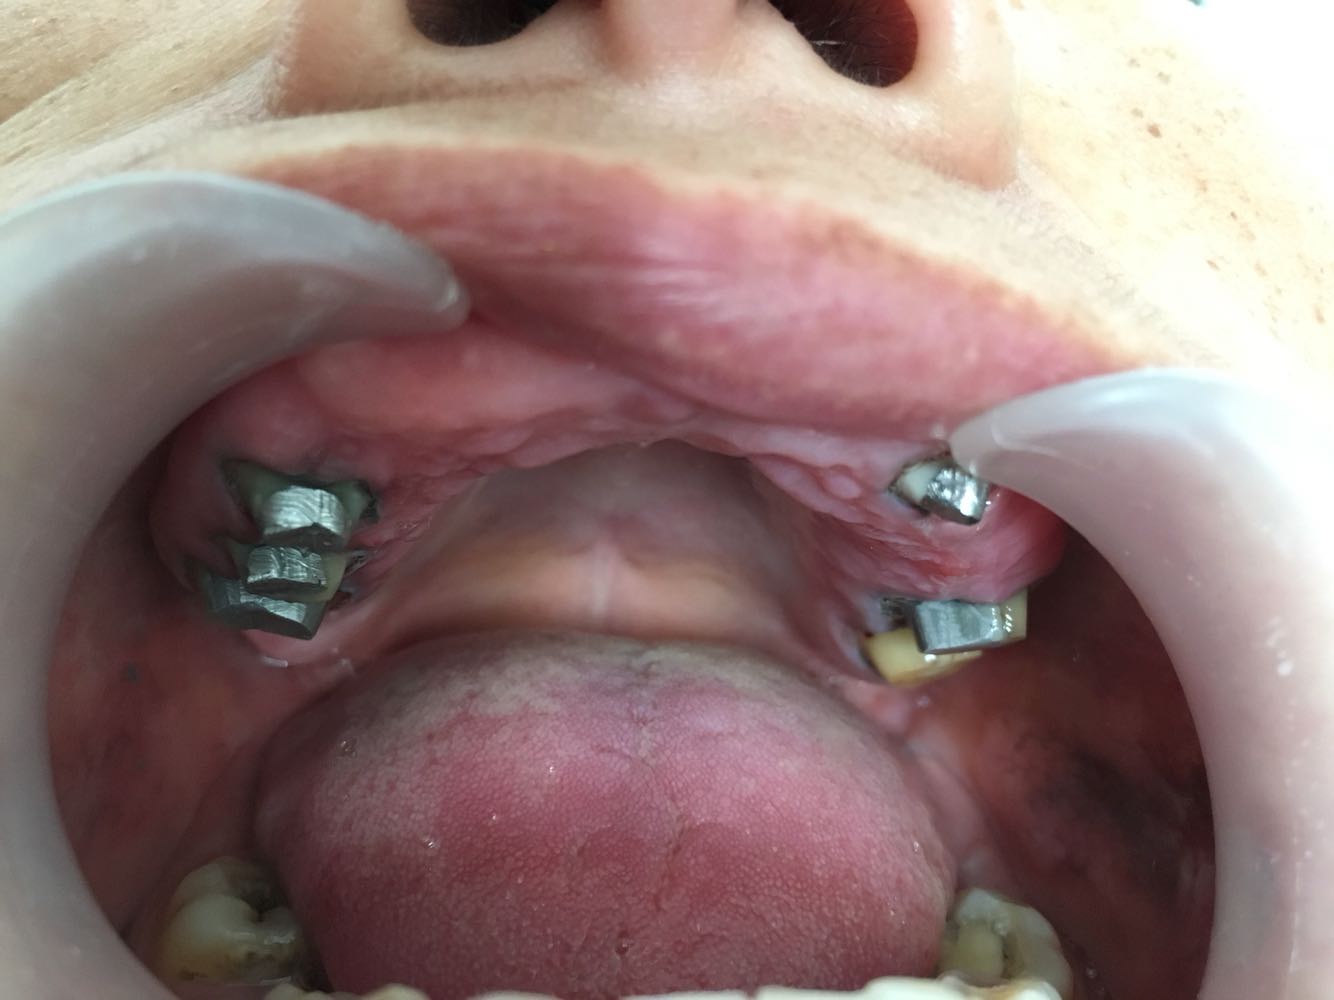

查体:11,12,13,17,21,22,24,25缺失牙槽嵴愈合好,14,15,16,23,26,27牙齿不同程度龋坏,下颌牙齿正常,部分牙齿伸长。

诊断:上颌牙列缺损, 治疗:下颌伸长牙齿调磨,口内上颌牙齿完善根管治疗,行套筒冠修复

随访:一次性试戴成功,咬合好,龈缘密合,定期口腔检查,嘱做好牙周维护。 讨论:套筒冠的适应症及制作技巧